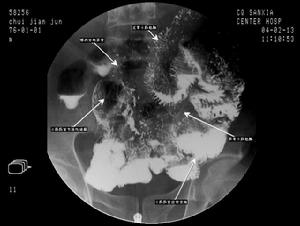

(5)胃腸X線檢查:小腸可有功能性改變,空腸中段及遠端腸管擴張,鋇劑通過不吝,黏膜皺裂粗大,腸壁平滑呈“蠟管”征,鋇劑分段或結塊(印痕征)。X線檢查還可排除腸結核克羅恩病等器質性疾病。

6、小腸鋇劑檢查: 注意病變部位及範圍,有無黏膜皺襞增粗增寬,鋇劑呈節段狀、絮狀或雪花狀分布,鋇劑排空時間延長。